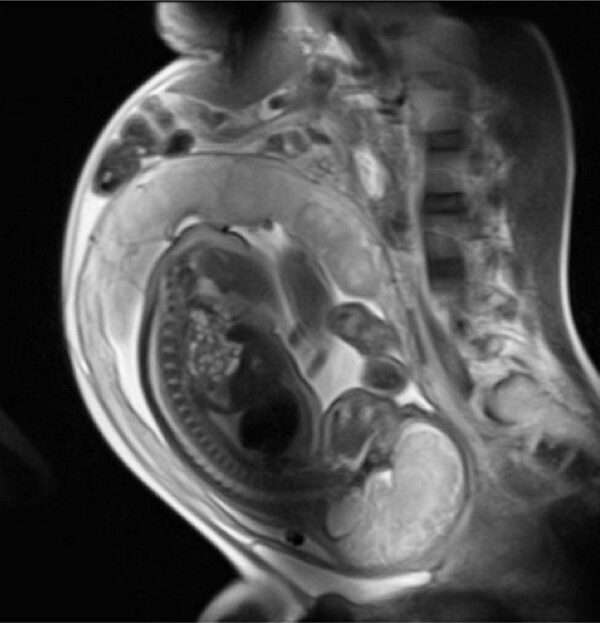

La sospecha de feocromocitoma se confirma mediante la medición de las metanefrinas fraccionadas libres plasmáticas en ayunas, obtenidas mientras la paciente se encuentra en reposo. Este análisis es altamente sensible para detectar la presencia de catecolaminas elevadas, que son las responsables de los síntomas característicos de la enfermedad. El aumento de las metanefrinas en plasma refleja la producción excesiva de estas sustancias por parte del tumor adrenal, lo cual es indicativo de feocromocitoma. Para confirmar la presencia de una masa en la glándula adrenal, la resonancia magnética (RM) es el método de elección, ya que ofrece una mayor precisión en la visualización de estructuras internas, en comparación con la ecografía, que tiene una menor capacidad para detectar tumores pequeños o localizados en áreas difíciles de alcanzar.